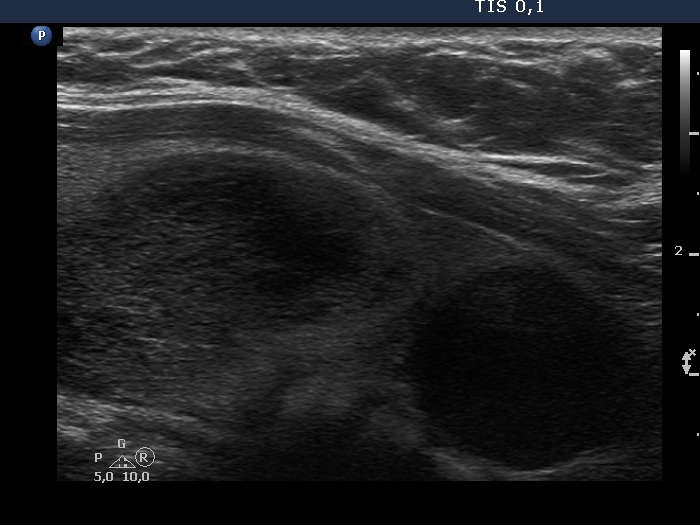

Follow-up investigation 3 years later (ultrasonographic picture 12)

Lower two third of the left lobe, longitudinal scan.